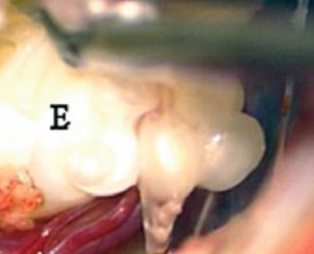

圖1?;颊邽橐幻?6歲女性,其Th7級腦膜瘤經(jīng)辛普森ⅱ級切除術(shù)治療,病理診斷為砂粒腦膜瘤。她在初次手術(shù)后9年腫瘤復發(fā)。核磁共振顯示(A)術(shù)前,(B)術(shù)后即刻,(C)初次手術(shù)后9年。